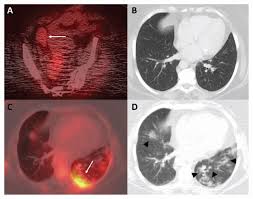

최첨단 현대의학으로 가장 적절한 방법이 양전자단층촬영술(Positron Emission Tomography, PET)이라고 나는 생각한다. PET는 체내 대사 변화를 촬영하는 기기로 CT나 MRI 다음에 개발된 영상장비이라고 한다.

요즘은 여기에 CT를 붙여서 PET 영상과 CT 영상을 융합해 서로 약점을 보완해 검사의 질을 더욱 높이고 있다고 한다.

여기에 방사성 핵종 F-18를 붙여(F-18 FDG라고 함) 혈관 주사하면 빨리 자리는 암세포는 포도당이 더 필요해 정상 세포보다 10∼100배 더 많이 모여들고 이를 방사능으로 촬영해 찾아낸다. 암이 1㎝만 돼도 10조개의 암세포가 있어 CT, MRI 소견이 애매한 경우 유용하게 쓰인다.

마지막으로 말씀드릴 점은 모든 초기 암을 PET 검진으로 해결할 수는 없다. 가령 위벽에 붙어 있는 0.5 cm 이하의 암이 포도당 대사마저 느리다면 알 수가 없기 때문이라고 한다.

PET 검사 후 반드시 경험 있는 의사 선생님과 상의하고 필요하면 내시경검사 등을 보완해야 한다. 어떤 최첨단 장비로도 암을 100% 찾을 수는 없다, 사실 그 일은 하느님의 영역이기 때문이라고 한다.